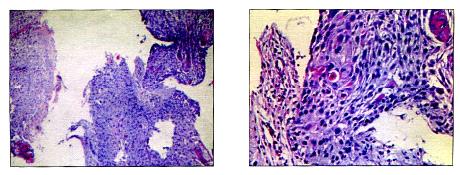

活检病理提示:(食管)鳞状细胞癌(图2)

图2